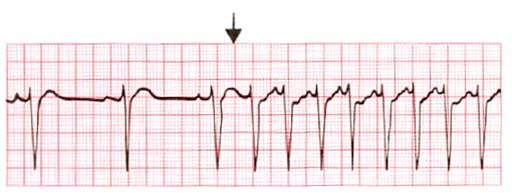

EKG

Dette er en smertefri og rask undersøkelse som kartlegger den elektriske aktiviteten i hjertet ditt. Det gjøres ved at elektroder festes til huden på brystkassen, armene og beina. Undersøkelsen viser om du har en pågående rytmeforstyrrelse, og den kan i noen tilfeller også påvise årsaken til en slik forstyrrelse. Denne undersøkelsen kan gjøres hos allmennlegen, og den kan i mange tilfeller være den eneste undersøkelsen som er nødvendig.